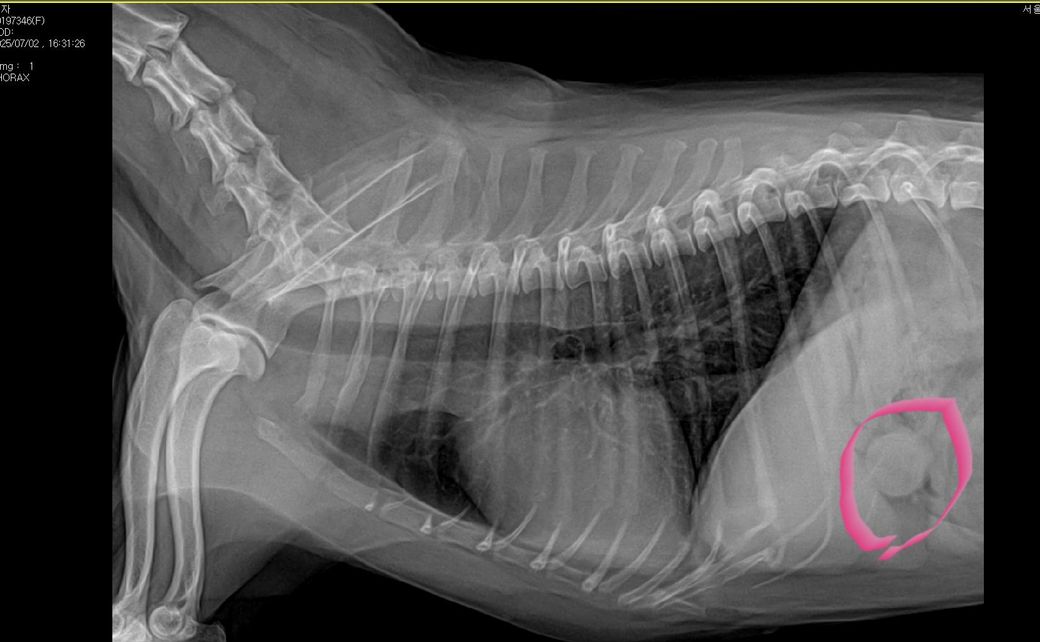

강아지 엑스레이 확인부탁드려요ㅠㅠ

안녕하세요 14살 강아지 투시촬영 엑스레이 사진인데요 분홍색 으로 체크한 동그랗게 있는게 무엇인가요? 종양인가요? ㅠㅠ뭔가요

위에 있는 물이 옆으로 눕힐때 유문부에 쌓인상태로 찍혀서 둥글게 보이는 대표적인 허상입니다.

정상입니다.